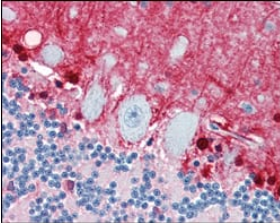

IHC    1/200 - 1/1000